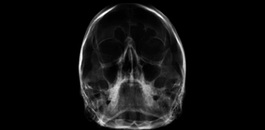

Seios da face digital

Muito utilizado para avaliação dos seios da face. Através do software romexis, podemos utilizar as ferramentas de inversão de imagem, brilho e contraste para uma avaliação mais precisa.

Póstero-anterior digital

Avaliação das estruturas da face.